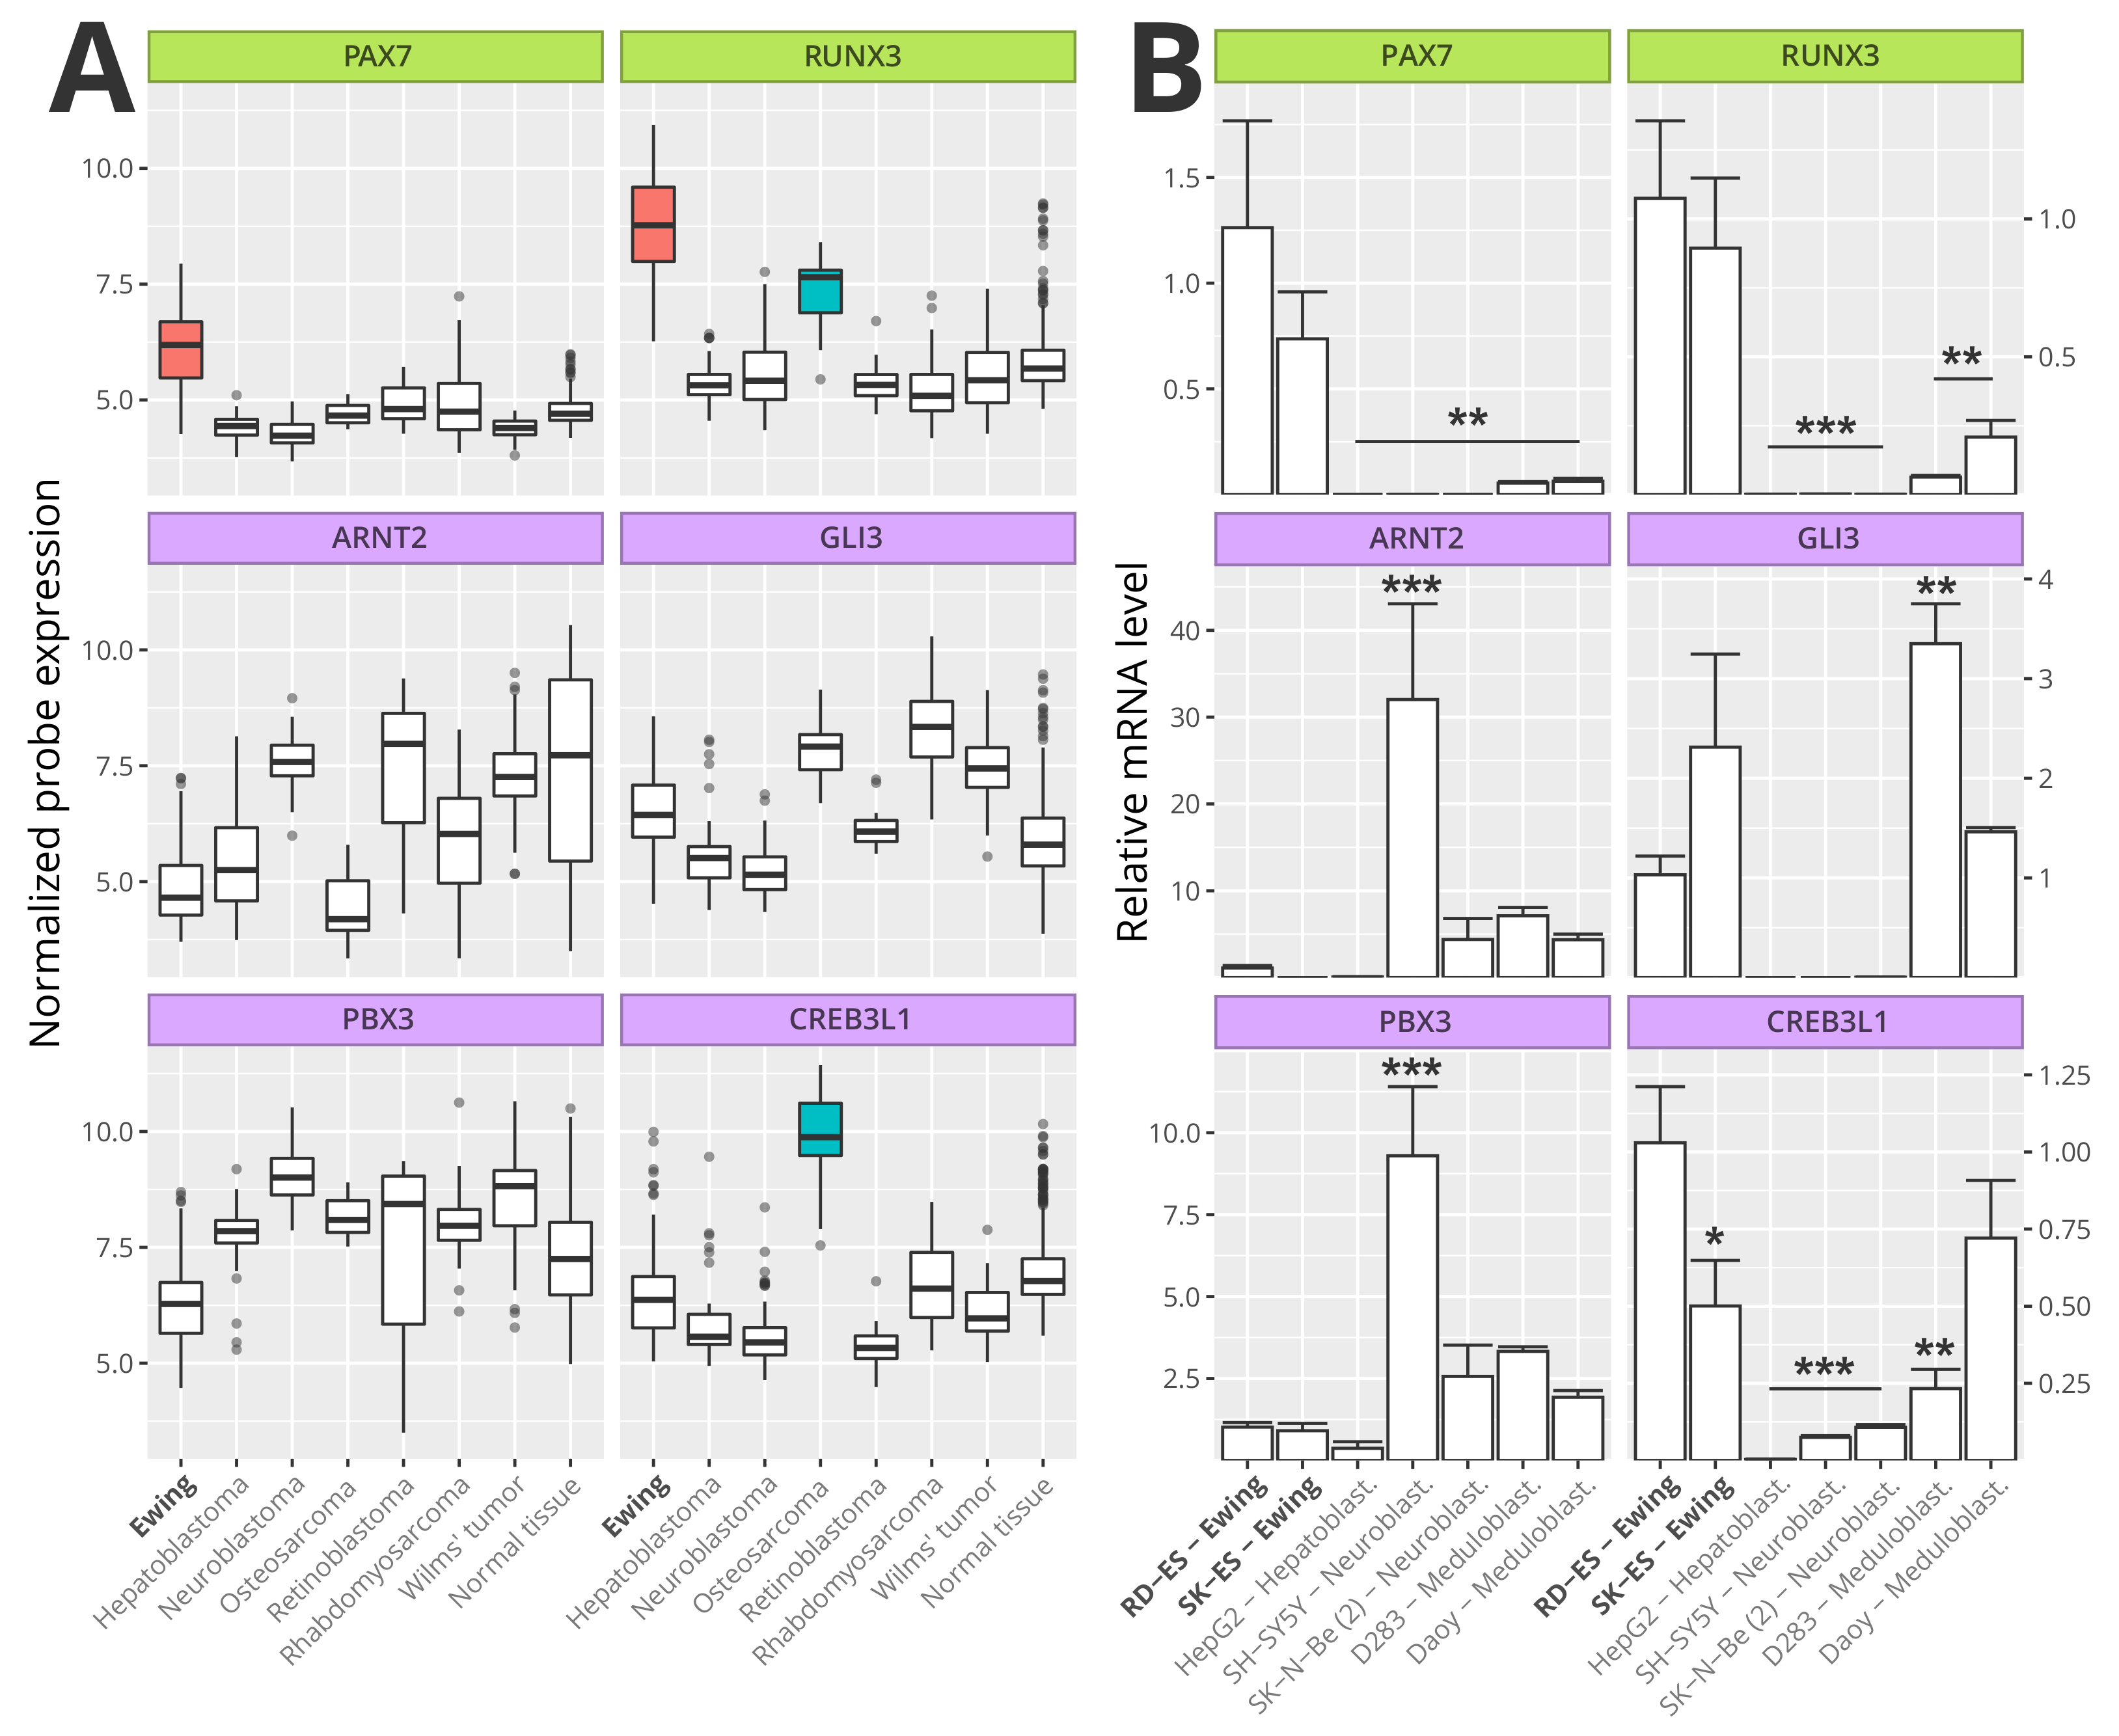

3.6. Master Regulators Expression in Ewing Sarcoma